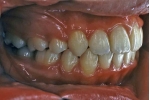

治療前後の比較